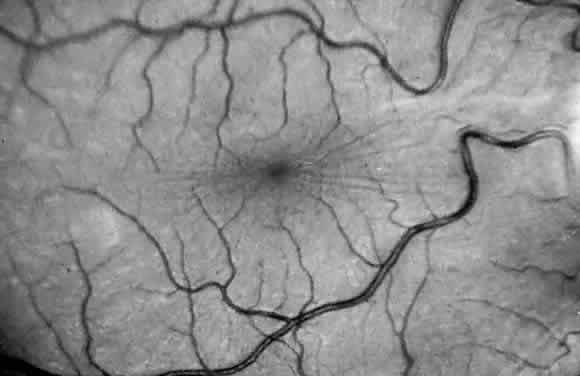

Corneal clouding (Fig. 10), hyperopic astigmatism, and a mild retinopathy with surface-wrinkling maculopathy (Fig. 11) appear to be the constant ocular triad.75 Some patients have retinal vascular tortuosity, optic nerve head swelling (Fig. 12), visual field defects, and abnormalities in color vision. Visual complaints are uncommon.

Fig. 11. Surface-wrinkling maculopathy in a patient with mucolipidosis III. (Traboulsi E, Maumenee I: Ophthalmologic findings in mucolipidosis III. Am J Ophthalmol 102:529, 1986)

Fig. 12. Optic nerve head swelling in a patient with mucolipidosis III. (Traboulsi E, Maumenee I: Ophthalmologic findings in mucolipidosis III. Am J Ophthalmol 102:529, 1986)